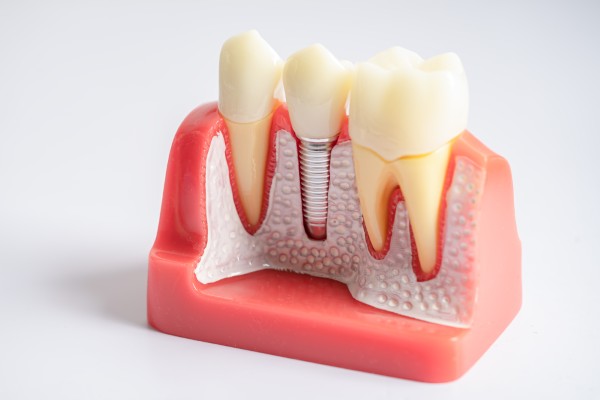

インプラント

自分の歯のようにしっかり噛める日常を

失った歯を補う治療として、顎の骨に人工歯根(インプラント)を埋め込み、その上に人工の歯を装着します。天然歯に近い見た目と噛み心地を再現できるのが特徴です。当院では、CT撮影による精密な診断を行い、安全で確実な治療計画を立てます。入れ歯やブリッジに比べて周囲の歯に負担をかけず、長期的な安定性が期待できます。